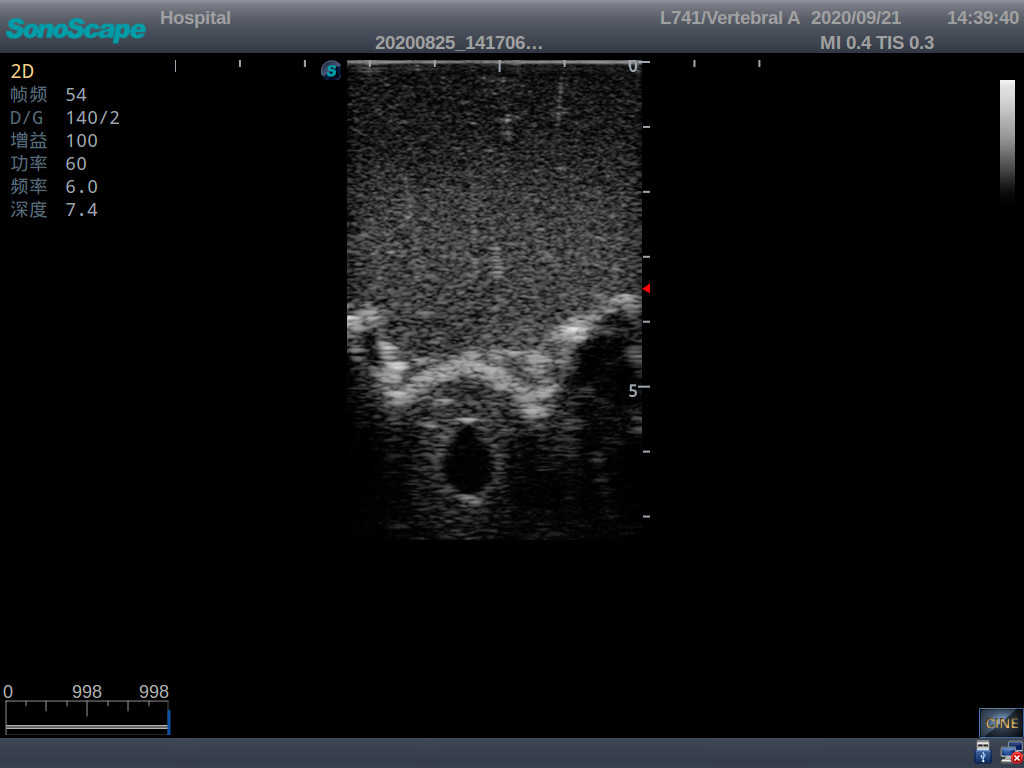

Adult Lumbar Puncture Ultrasound Training Model

This model is an ideal choice for ultrasound-guided adult lumbar puncture training with true-to-life skin feel and touch, accurate anatomical structures as well as real clinical ultrasound images. Realistic resistance to needle tips and correct landmarks provide excellent hands-on experience.

Accurate anatomical structure of L1-L5 and the vertebral canal

2)  Real clinical ultrasound images

3)  Compatible with various real ultrasound machines

1)   Ultrasound-guided lumbar puncture practice